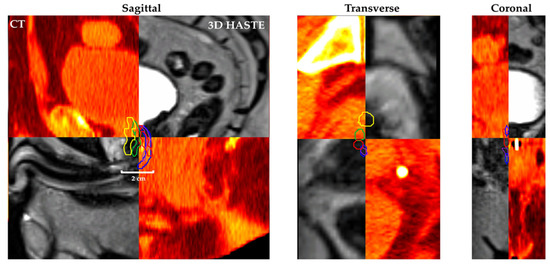

Figure 3 shows Patient 11’s (Figure 3a) planning CT, (Figure 3b) 2D diagnostic T2w MRI, (Figure 3c) MRgRT 3D HASTE, (Figure 3d) MRgRT 3D TSE, and (Figure 3e) clinical MRgRT 3D bSSFP. In the planning CT, there is no tissue contrast between the urethra and prostate. In the MRI scans, the contrast is improved in general, but urethra visibility varies in different MRI sequences. Notably, diagnostic MRI and MRgRT 3D HASTE and TSE showed less motion/ghosting artifacts, compared to MRgRT 3D bSSFP (blue arrow).

Figure 3. Patient 11’s (a) planning CT, (b) 2D diagnostic T2w MRI at 3T, (c) MRgRT 3D HASTE, (d) MRgRT 3D TSE, and (e) clinical MRgRT 3D bSSFP (red arrows pointing to the prostatic urethra). Blue arrows showing different amounts of motion/ghosting artifacts in each MRI image. Clinical MRgRT 3D bSSFP showed significant motion/ghosting artifacts.